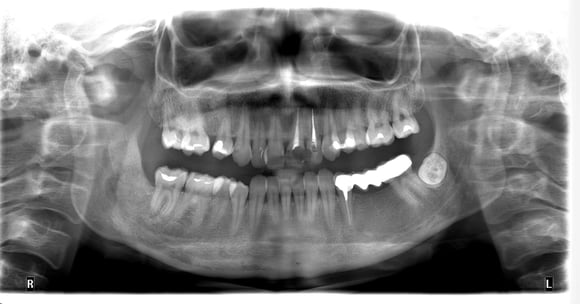

Дистопія зуба мудрості

ОПГ після операції